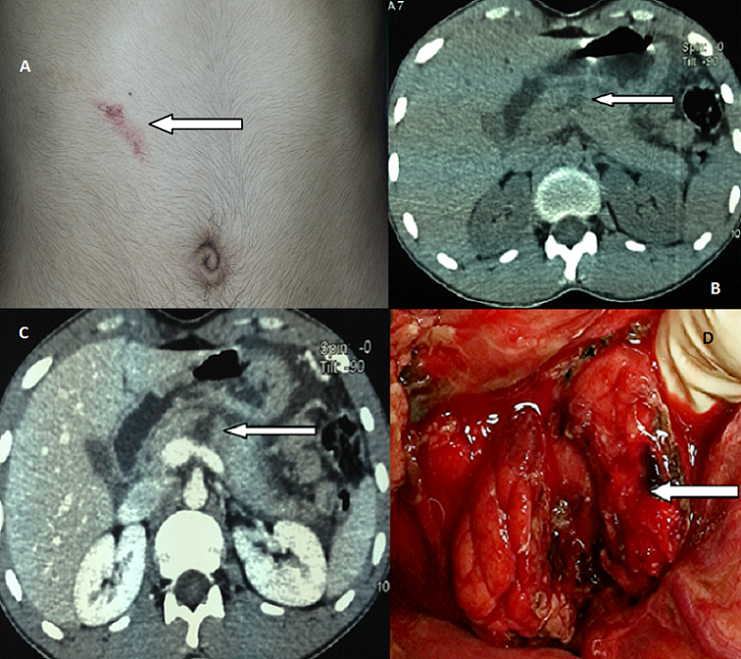

Les traumatismes du pancréas sont rares. Ils constituent 0.2 à 6 % de l’ensemble des traumatismes de l’abdomen. Le traumatisme isolé du pancréas est peu fréquent et de diagnostic souvent difficile Nous rapportant le cas d’un patient de 20 ans maçon de profession qui a été admis aux urgences pour prise en charge des épigastralgies secondaires a un traumatisme abdominale fermé du a un coup accidentel par un bâton de fer datant de plus de 48 heures. L’abdomen était sensible, la lipasémie était à 10 fois la normale. La TDM montrait une fracture isthmique du pancréas avec un épanchement abdominale de moyenne abondance. Le patient a été admis en urgence au bloc opératoire; il a bénéficie d’une anastomose pancréaticojéjunale; l’évolution été favorable. La rareté des Traumatismes isolés du pancréas et leur symptomatologies cliniques atypiques au stade de début rend leur diagnostic relativement difficile d’autant plus que la biologie n’est pas spécifique. Ceci doit nous pousser à réaliser des TDM devant tout traumatisme épigastrique même s’il n’est pas violent.